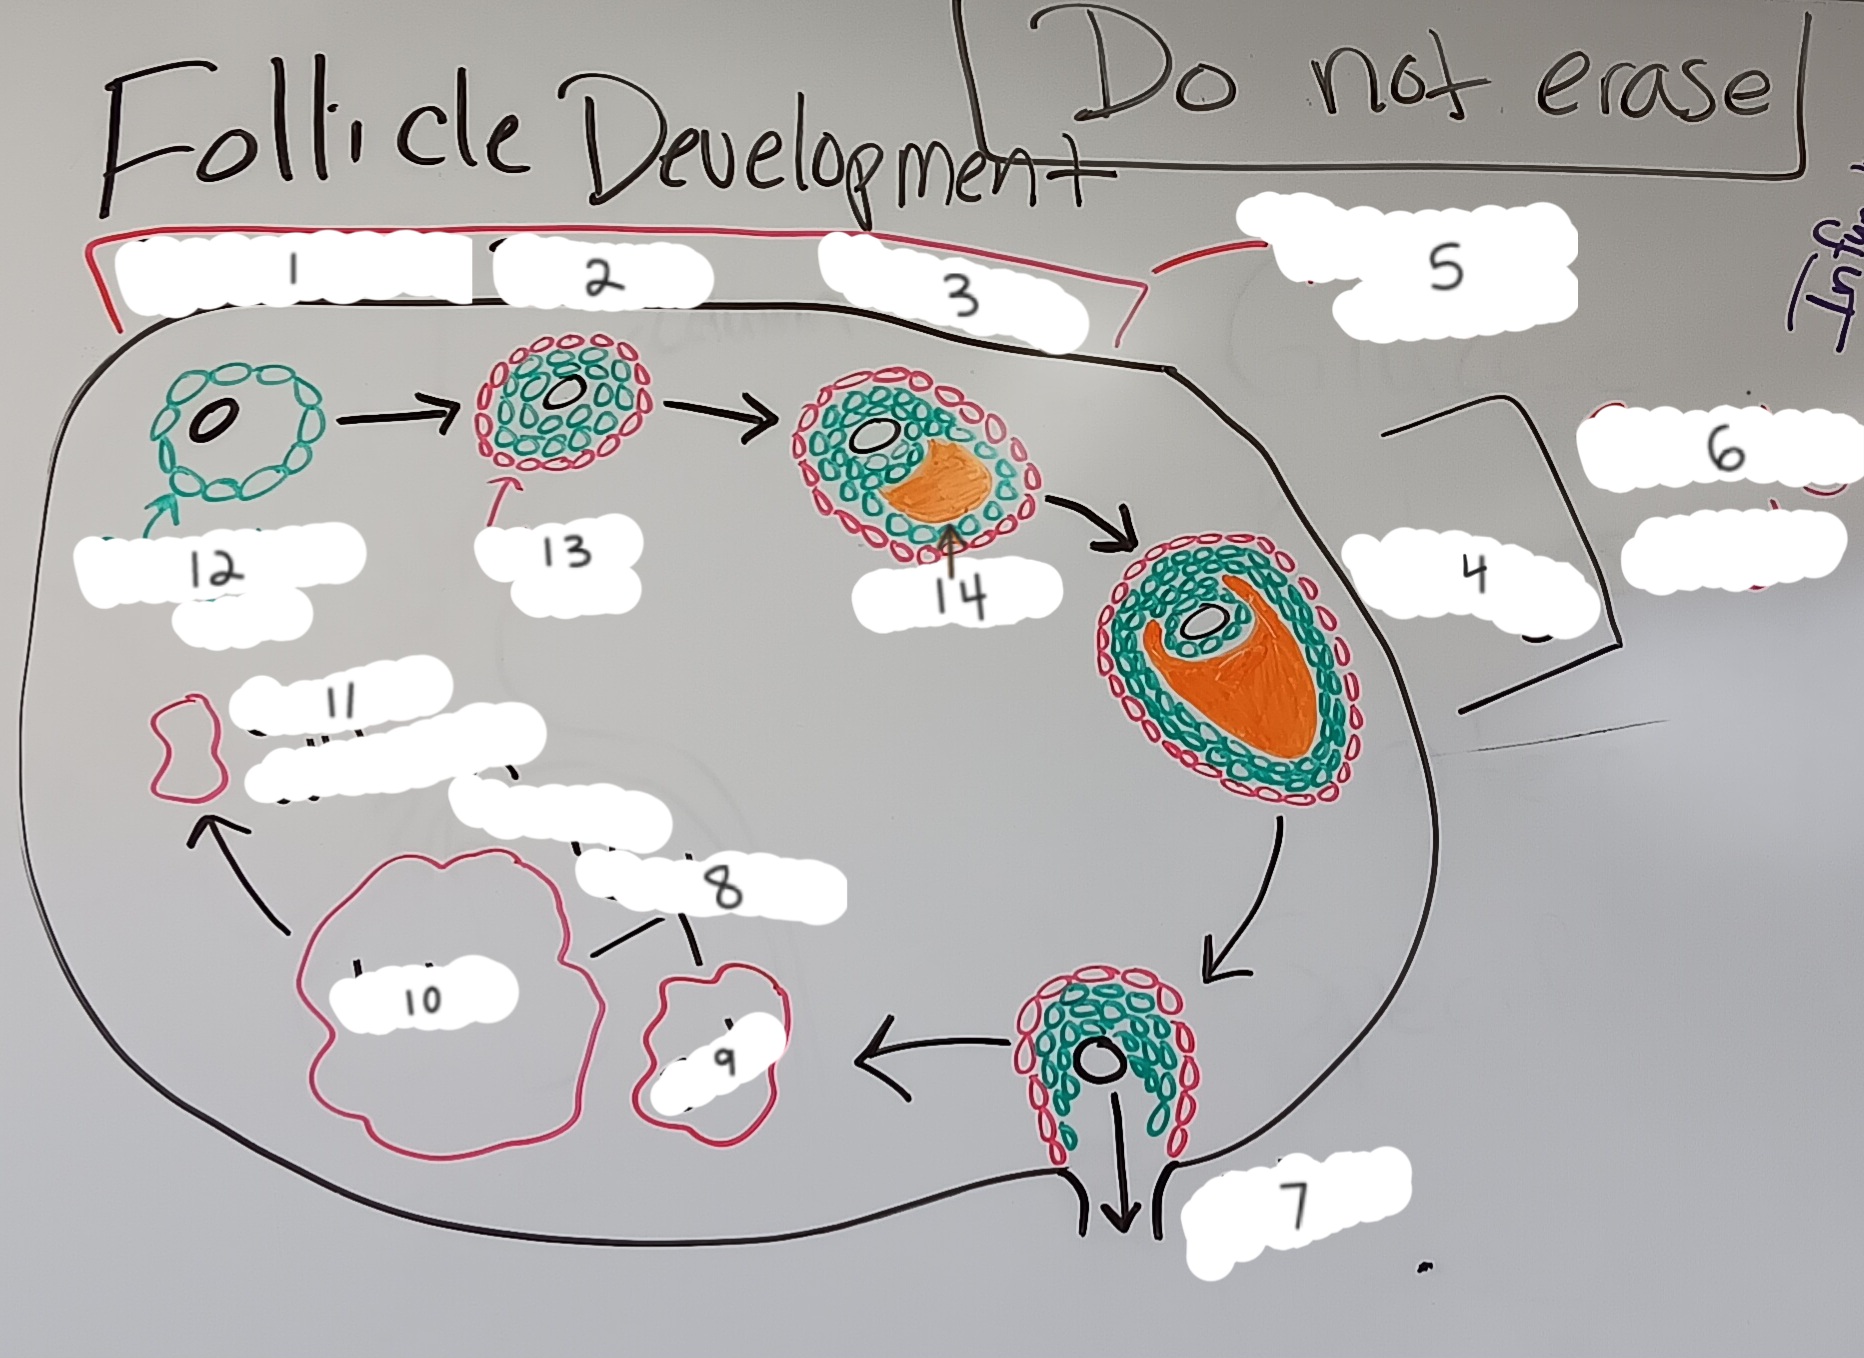

Primordial follicle

1

Primordial follicle

Primordial follicle

1

Primary follicle

2

Primary follicle

Primary follicle

2

Secondary follicle

3

Secondary follicle

Secondary follicle

3

Tertiary follicle

4

Tertiary follicle

4

Mature follicle

5

Mature follicle

Mature follicle

7

Antrum

10

Zona pellucida

9

Theca folliculi

8

Corona radiata

Corpus luteum

Corpus luteum

Corpus albicans

Corpus albicans

corpus luteum

8

early corpus luteum

9

late corpus luteum

10

corpus albicans

11

granulosa cells

12

theca cells

13

antrum

14